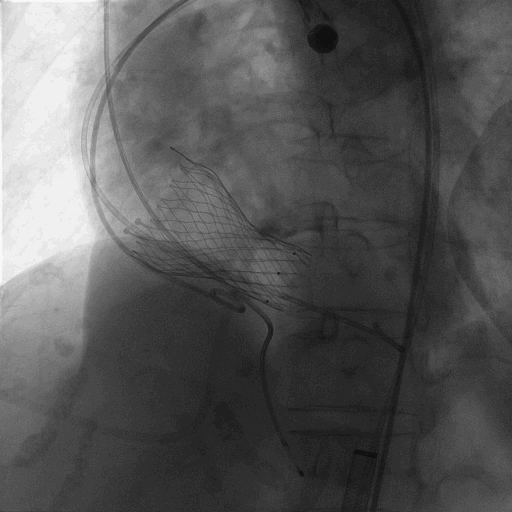

术中造影

植入L26 VenusA-Plus瓣膜,标准位释放,释放到2/3,观察瓣膜位置,以及再次确认冠脉风险,左冠正常显影,选择全部释放。

造影可见轻微瓣周漏,与FEops预测一致。

患者狭窄解除,流速明显降低,跨瓣压差降为0,超声显示轻微瓣周漏(与FEops预测结果一致),术中及术后未出现相关并发症,手术圆满成功。